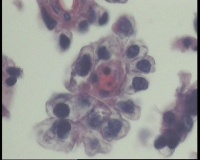

| 一般病史 | 彩超:盆腔可见囊实性回声,囊性为主,大小约5.0x3.7厘米,其内可见分隔回声,部分分隔内回声不纯净,形态欠规整 | ||||

| 标本名称 | 腔镜下右侧卵巢囊肿手术 | ||||

| 大体所见 | 囊壁样组织5.5x5.0厘米,4.5x2.5厘米2块,壁厚0.1-0.2lm,囊壁大部分光滑,局灶见0.7x0.5x0.3厘米淡黄色突起组织,另见淡黄色、肉粉色质软组织2.8厘米一堆。 | ||||